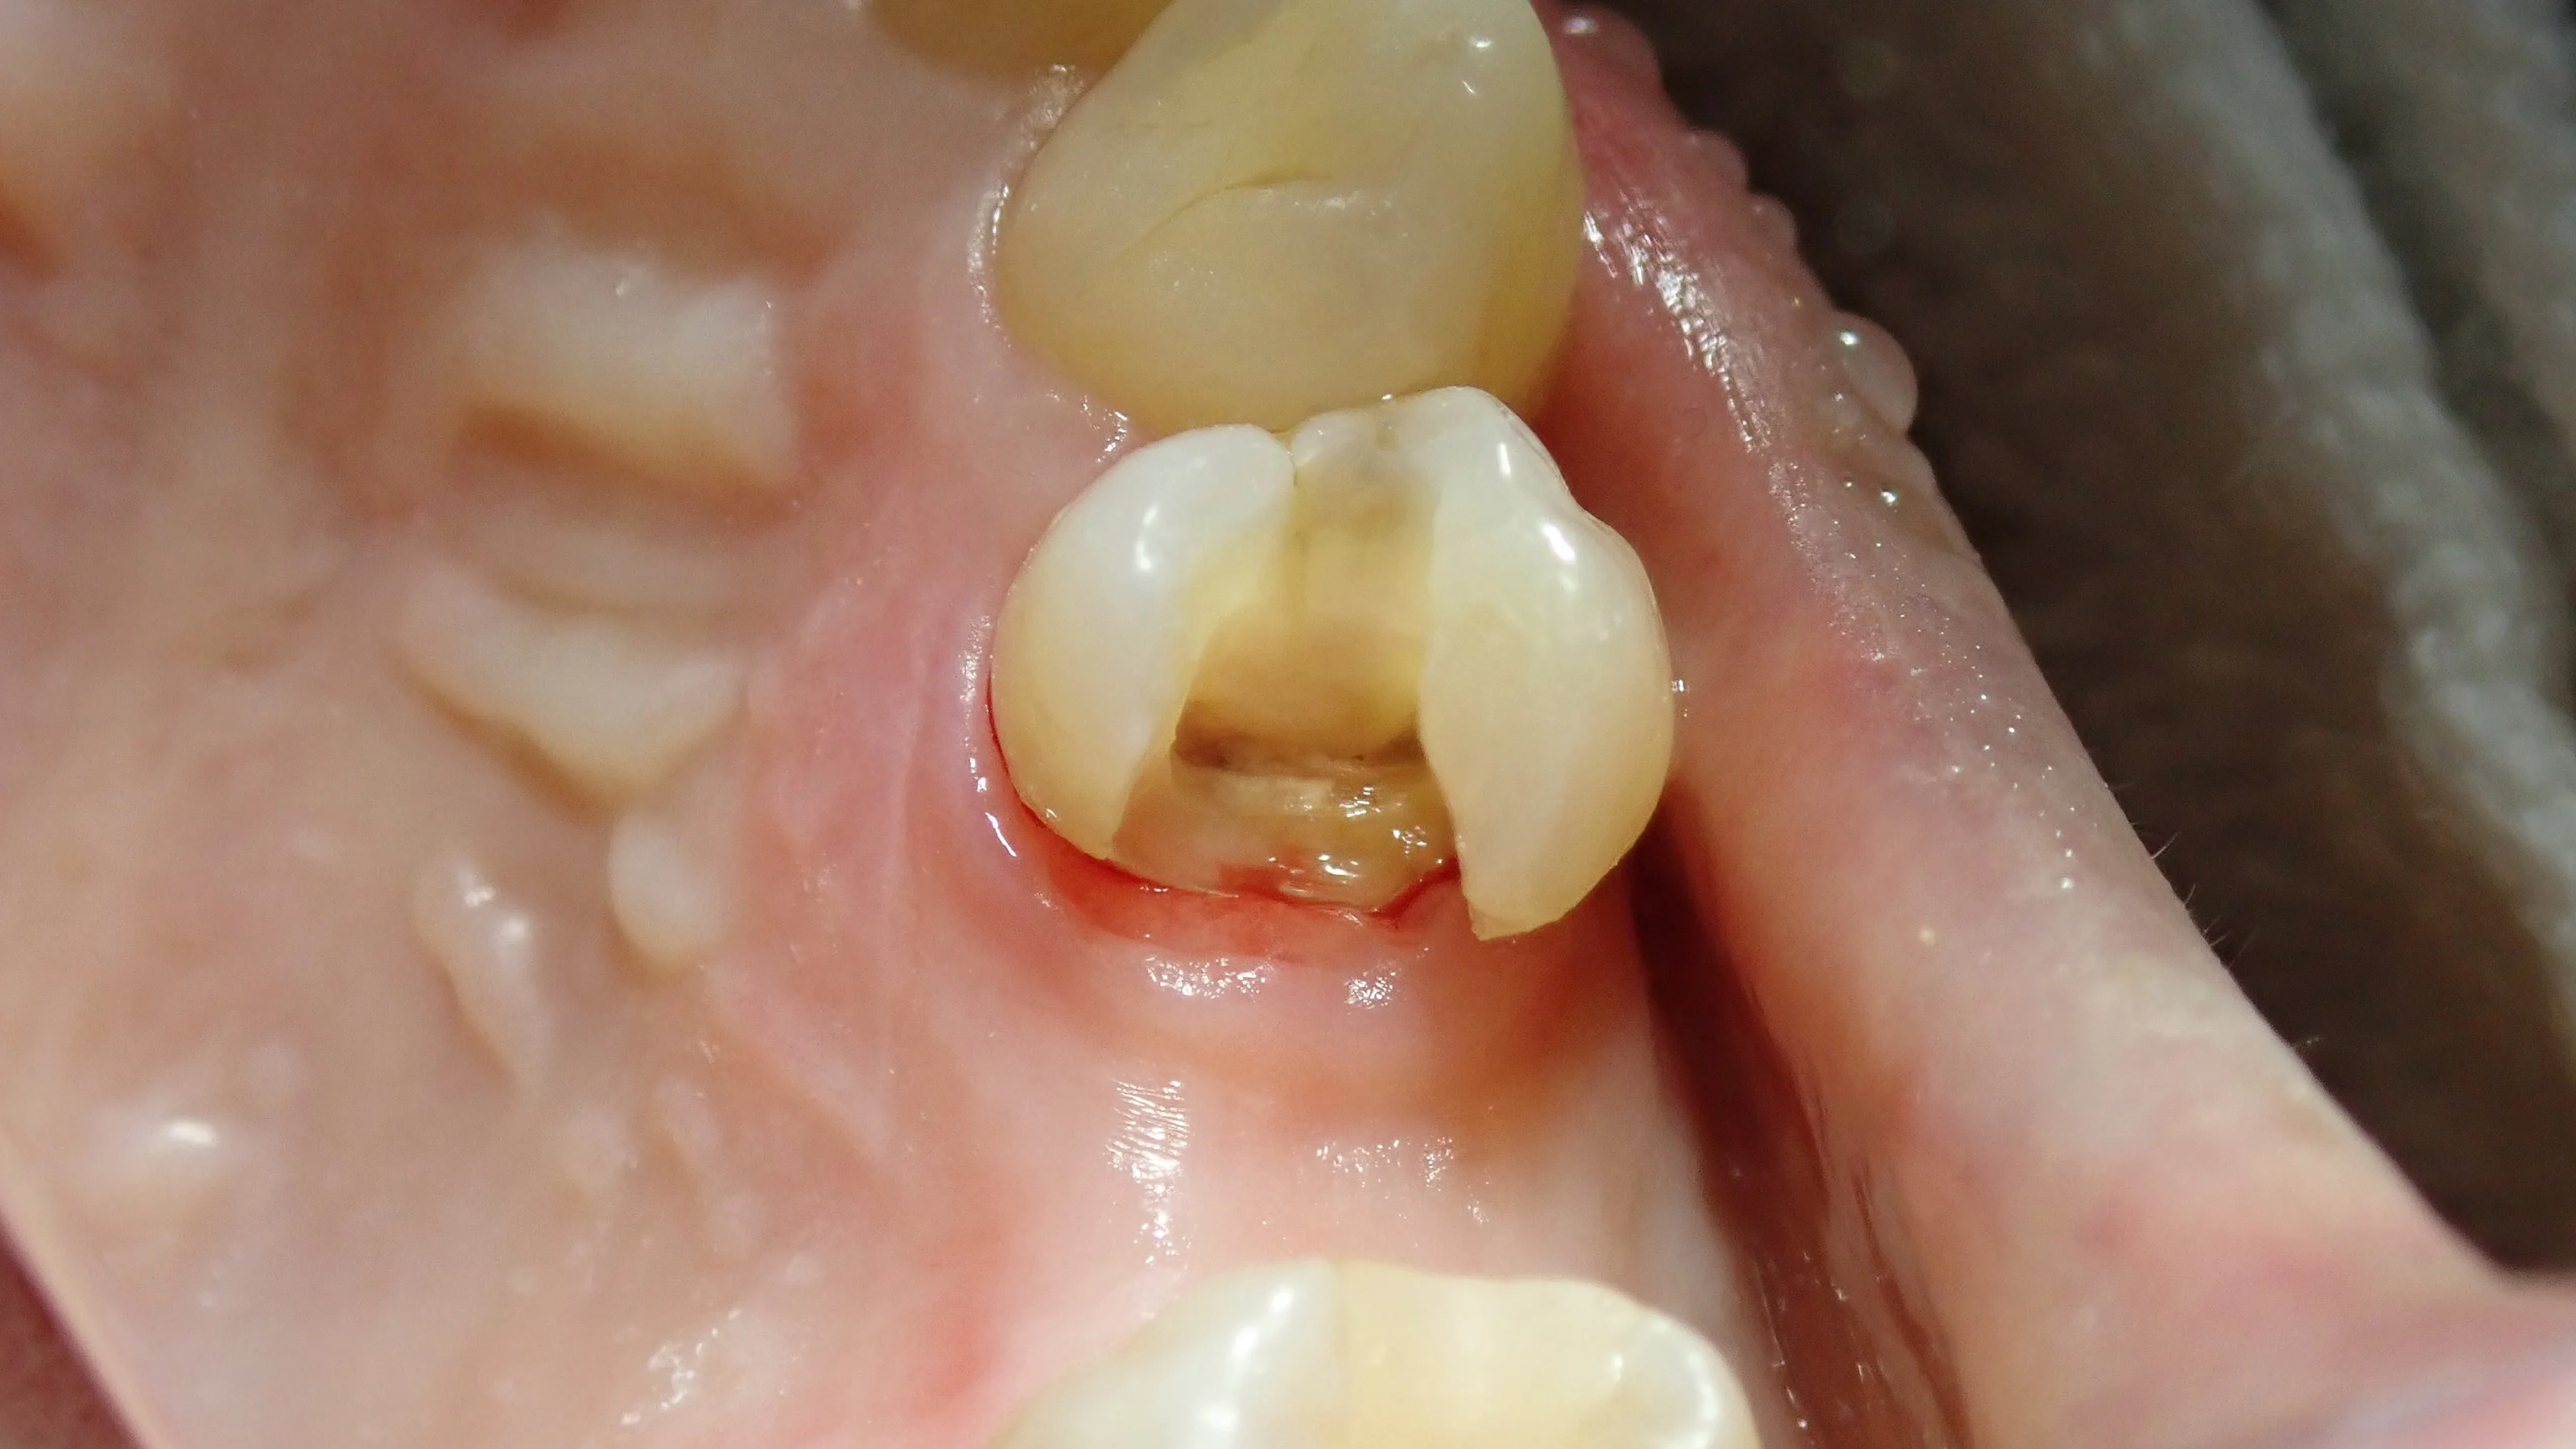

術前の状態です。

元々白い詰め物が詰められていますが、亀裂が入っており、その付近から虫歯が黒く透けて見えています。